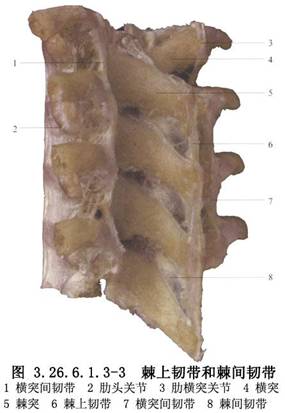

脊柱節段性器械是1973年Luque首先創用的,其特點是在脊柱矯形區內的多個椎體節段上,用鋼絲通過椎板下或棘突基底部將矯形棒固定於椎體上進行脊柱矯形。Luque棒和記憶合金棒均屬於脊柱節段性器械。手術相關解剖見下圖(圖3.26.6.1.3-1~3.26.6.1.3-3)。

沿棘上韌帶切開,顯露至棘突,先行脊柱凹側面分離。使用Cobb剝離器以棘突爲支點,緊貼棘突及椎板骨面向外側推開椎旁組織直到關節突,邊剝離邊用紗布填塞止血,依次行相鄰椎板分離顯露。胸椎向兩側顯露至橫突尖,凸凹側均行廣泛鬆解,切除橫突間韌帶及肌肉,胸腰椎均行關節切開術。